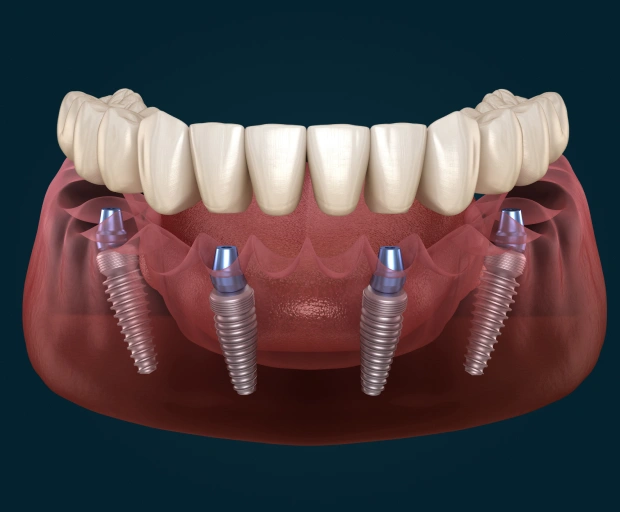

Maintain optimal oral function and aesthetics with All-on-4 same-day teeth replacement. Using state-of-the-art technology, All-on-4 treatment replaces traditional dentures, which can be uncomfortable, inconvenient, and poorly fitted. All-on-4 turns problematic chewing and speaking into relics of the past.

Using only four dental implants to attach a full dental restoration, Dr. Bally can give you the stable, functional, and cosmetic solution you’ve been looking for. Best of all, your dentures can be placed on the same day as your implants, so you don’t have to wait to get the restored smile you deserve.

- Because All-on-4 allows full-arch restoration with only four implants, your treatment and recovery time are greatly reduced.

- All-on-4 lowers the need for bone graft surgery while ensuring greater stability in the existing bone. It can even be used for patients who have been told they do not qualify for implants due to bone loss.

- The All-on-4 solution is more comfortable than traditional dentures because All-on-4 implants are more secure and feel like natural teeth.